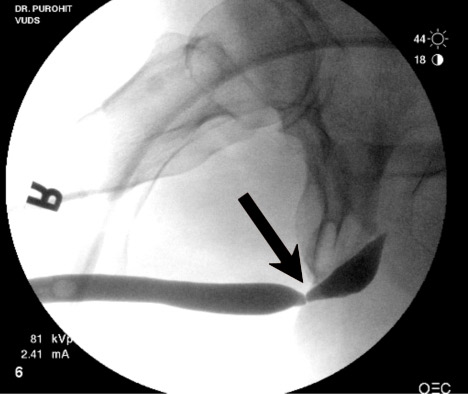

Bác sĩ cũng có thể chụp niệu đạo ngược dòng để xem xét. Trong phương pháp này, thuốc cản quang được đưa vào niệu đạo để đánh dấu ranh giới của nó và tìm vị trí và chiều dài của chỗ hẹp. Đây là kỹ thuật rất hữu ích để đánh giá chỗ hẹp.